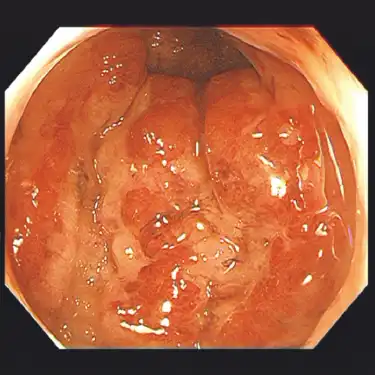

治療後(半年後) -

大腸粘膜の炎症を抑え、症状をコントロールすることで日常生活を病気発症前と同じレベルで行えるようにすること(臨床的寛解)が第一の目標となります。また症状がなくても内視鏡で炎症が残存していると再燃のリスクと大腸がんの発症リスクが増加することが知られており、定期的な内視鏡検査と治療の継続が非常に重要になります。

十分な寛解が維持できていれば健康寿命は病気のない人と大きく変わりはないという報告もあり、実際に社会で活躍している著名人の方も多く見られます。